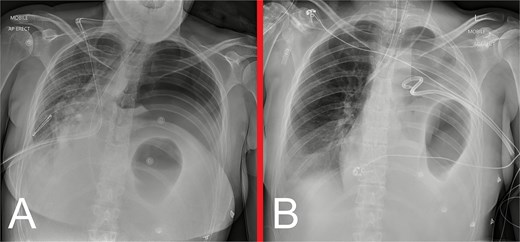

On initial examination, she was haemodynamically stable, with epigastric and left upper quadrant tenderness, but no peritonism. A venous blood gas showed a lactate of 2.7, but no acid–base disturbance or respiratory failure. Chest X-ray (CXR) revealed left hemidiaphragm effacement and a large air-fluid level in the left hemithorax (Fig. 1). A thoracoabdominal computed tomography (CT) scan revealed a markedly dilated stomach displaced into the left hemithorax, suggestive of a large, incarcerated left DH (Fig. 2). A nasogastric tube (NGT) was inserted for immediate gastric decompression (Fig. 1). An emergency gastroscopy confirmed a DH with displacement of the whole stomach into the chest. Endoscopic pyloric cannulation was impossible due to the herniated stomach’s configuration, but there was no mucosal damage, transmural necrosis, or gastric volvulus. Therefore, NGT decompression was continued as a temporizing measure, with planned semi-urgent definitive repair within a few days.

(A) Anteroposterior and (B) lateral view CXRs taken during the patient’s initial presentation, demonstrating effacement of the left hemidiaphragm outline, with a large air-fluid level within the left hemithorax and no evidence of a pneumothorax. (C) Anteroposterior view CXR following urgent NGT insertion for gastric decompression with its tip projecting over the stomach, with associated compressive atelectasis of the left lung.